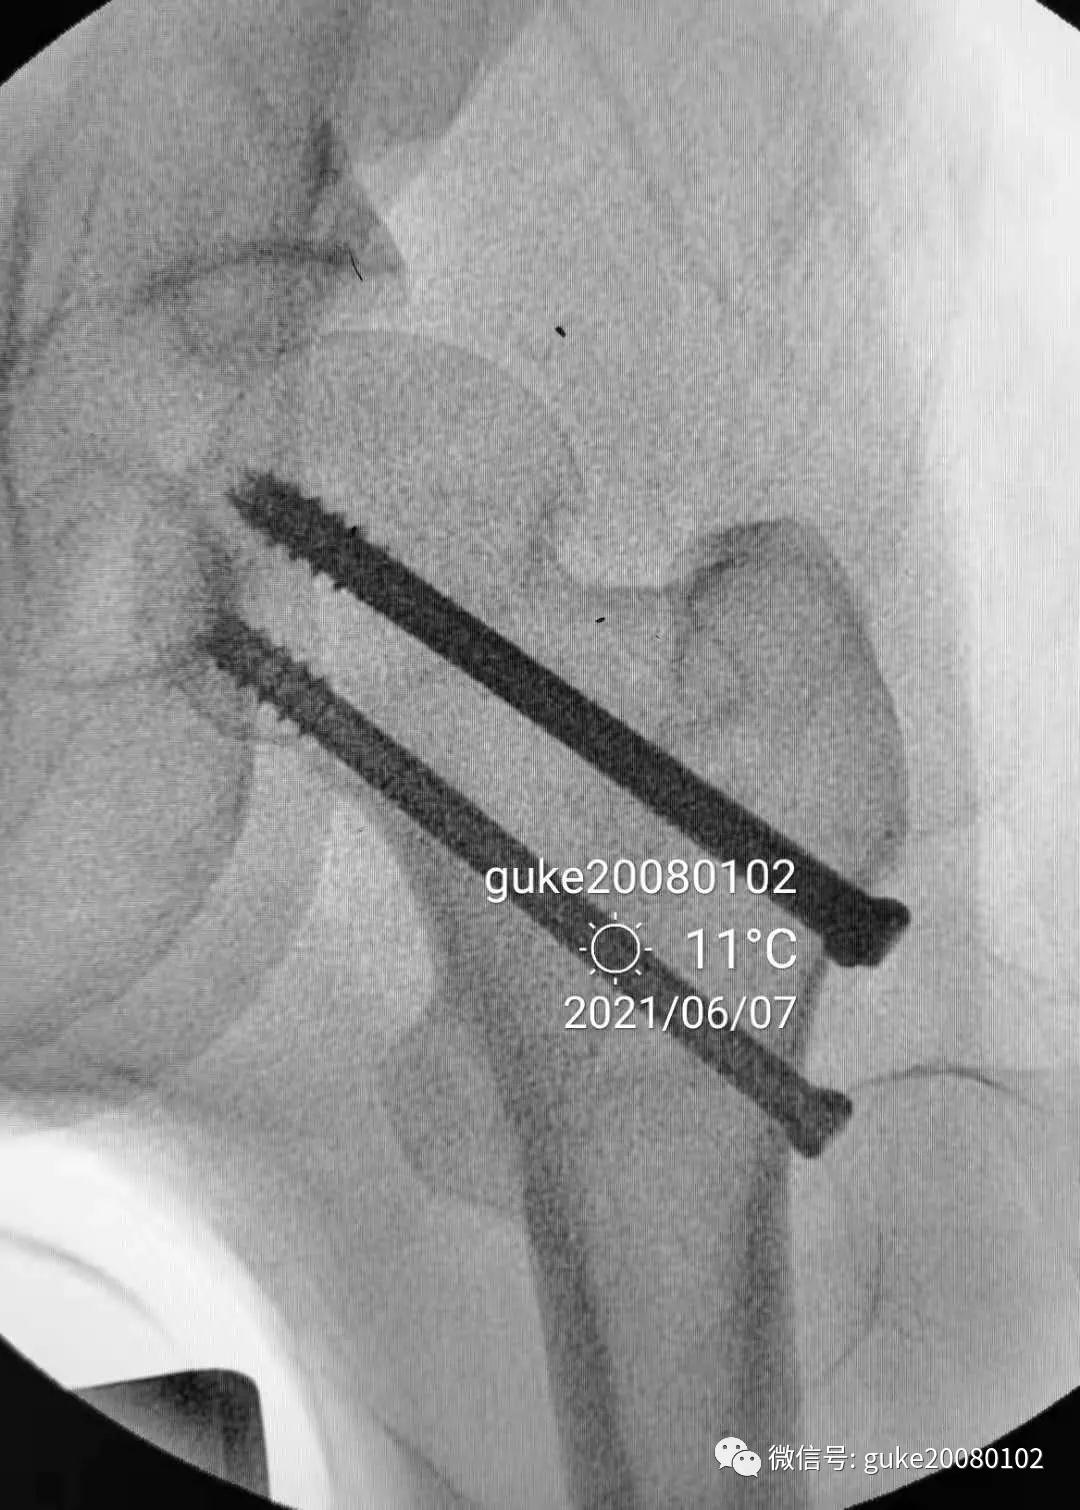

1.顺导针切开皮肤后,空心钻大转子外侧壁开口。

2.拧入三枚直径7.3mm空心钉,并逐步加压,稳定骨折断端。

最后透视: